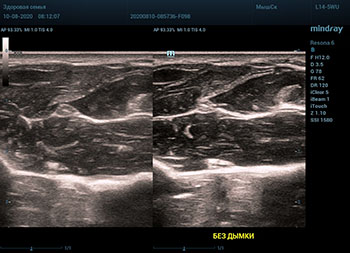

Ультразвуковое оборудование не отстает от современно тренда. В приборах серии Resona, компании Mindray, появилась новая функция постобработки изображения. Имя ей Dehaze. В переводе на наш родной язык – удаление дымки или рассеивание тумана. Инструмент позволяет корректировать интенсивность тумана или дымки. При этом сохраняется общий контраст и детализация картинки. Dehaze также позволяет проявлять детали снимка в гиперэхогенных зонах и снимать артефакты при чрезмерном усилении.

Готовый снимок или видео петля в формате DICOM несет в себе полное нативное изображение. Прибор позволяет, подобно легендарному фотошопу, удалить лишний «туман». Гиперэхогенный диффузный «засвет» изображения, из-за повышенного общего усиления, часто вредит обследованию. Однако без него некоторые вещи не видны. Показать гипоэхогенные участки и скрыть эхогенную дымку и позволяет Dehaze.

Всё что требуется от доктора – нажать кнопку или повернуть ручку. Мгновенная оптимизация. Мгновенно чистое изображение.